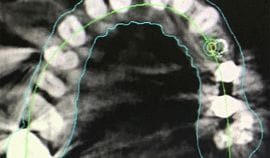

Screenshot of a computer generated CT guided implant model

Guided implant surgery is a breakthrough technology which offers benefits previously unknown in implant dentistry. Guided implant surgery is a procedure in which precision surgical instrumentation is used in conjunction with three-dimensional CT images. Dedicated computer software, which allows visualization and manipulation of the images of the patient’s jaw bone and surrounding tissue, makes it possible for the most accurate approach to implant surgery. Traditional surgical guides are difficult to use predictably when there are no apparent anatomic references.

At Terrace Oaks Dental, we used Vatech Green CT in conjunction with our digital impression to create a perfect plan for our implant surgery cases.